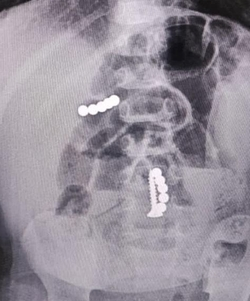

Родители годовалого ребёнка в Ставрополе позвонили в скорую с жалобами на плохое самочувствие малыша. Дежурный хирург в больнице обнаружил инородные предметы в теле мальчика, и пациента срочно прооперировали. Об этом рассказали в краевом минздраве.